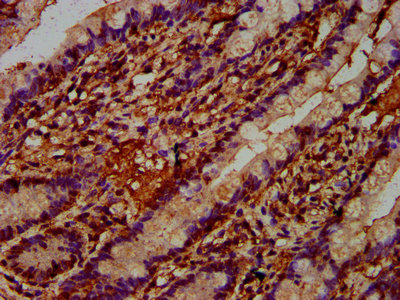

IHC (Immunohiostchemistry)

(IHC image of AAA234902 diluted at 1:400 and staining in paraffin-embedded human colon cancer performed on a Leica BondTM system. After dewaxing and hydration, antigen retrieval was mediated by high pressure in a citrate buffer (pH 6.0). Section was blocked with 10% normal goat serum 30min at RT. Then primary antibody (1% BSA) was incubated at 4 degree C overnight. The primary is detected by a biotinylated secondary antibody and visualized using an HRP conjugated SP system.)